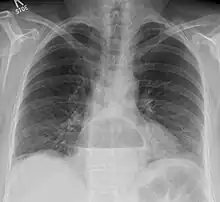

- Radiographie thoracique : visualise parfois la hernie.